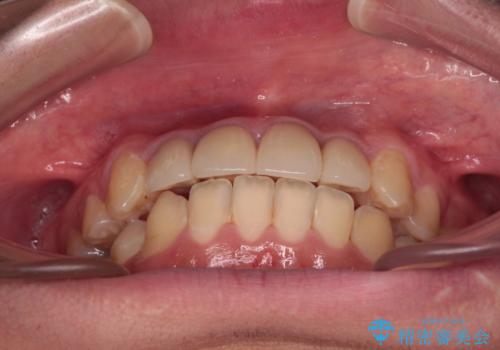

前歯のデコボコとむし歯だらけの歯列 矯正治療と虫歯治療

- 10代男性(高校生)

- むし歯が多く、歯並びも悪いとのことで、以前通院されていたご家族の紹介で来院された患者様です。

口腔内に無頓着であったため、まずはしっかりと歯磨きトレーニングを行い、必要な虫歯治療を行いました。

矯正治療は、むし歯が酷く抜歯が望ましい歯を1本抜歯して、ワイヤー装置にて整えることとしました。

矯正治療後は上顎前歯4本をオールセラミッククラウンにて補綴治療を行うこととしました。